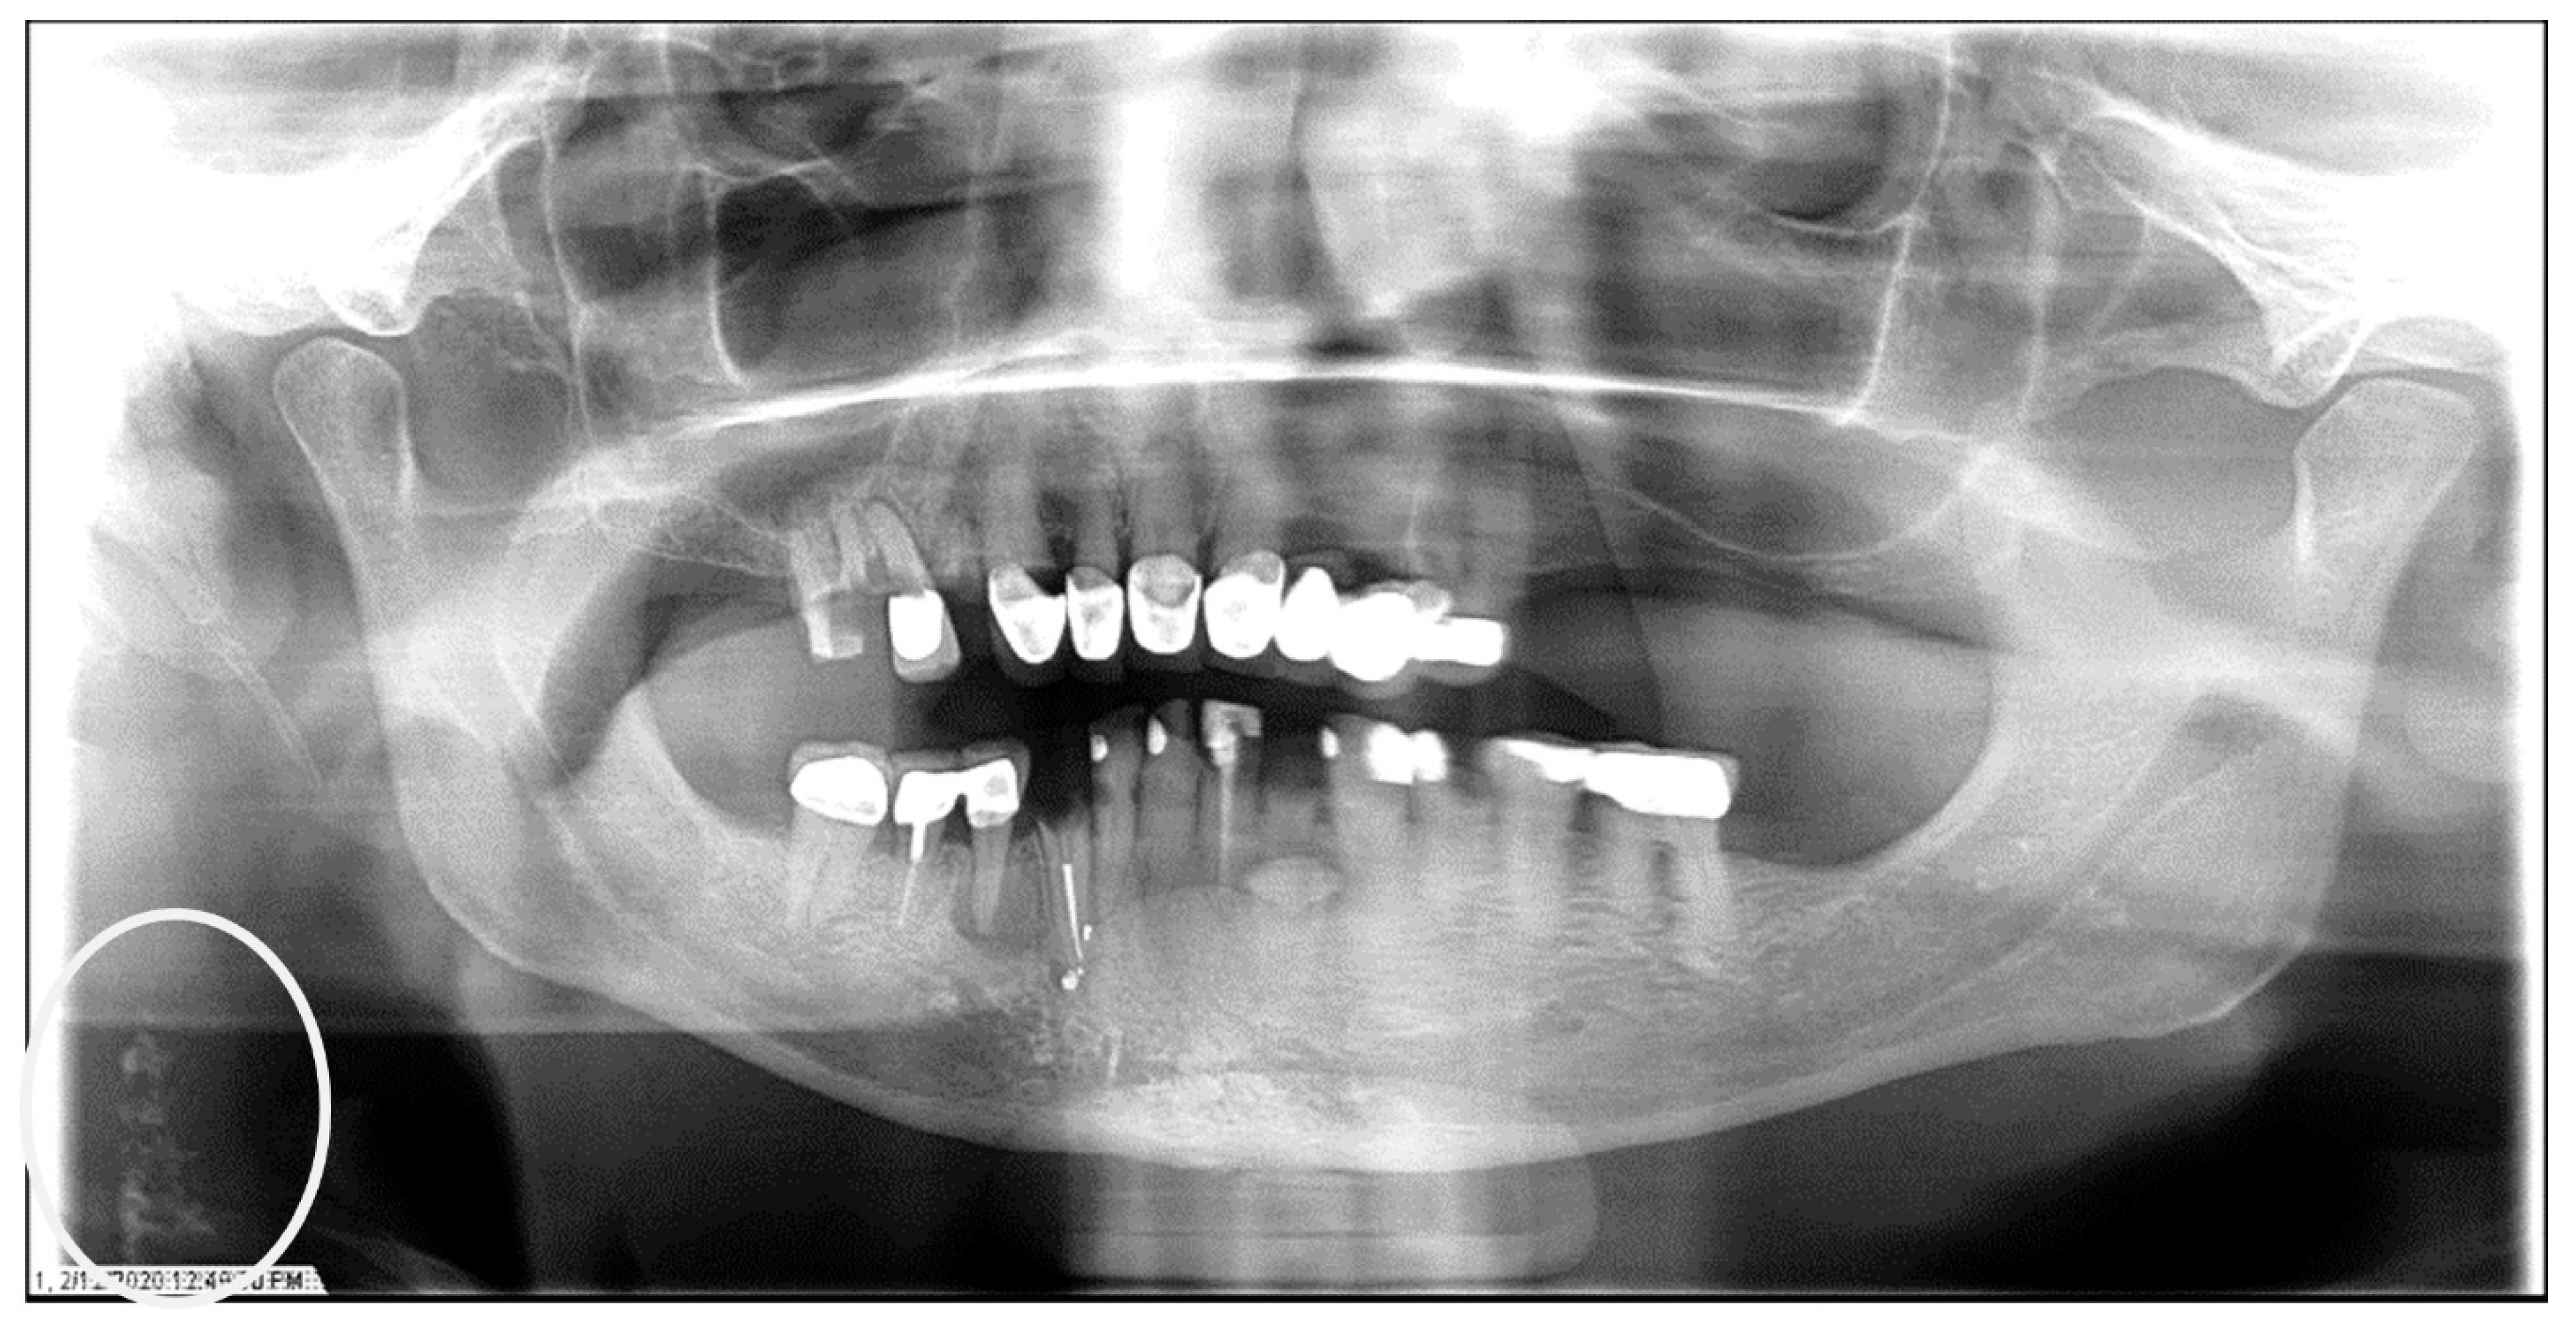

The characteristics of the CAC patients are presented in Table 1. Between 2014 and 2023, there were 559 patient records with the terms “carotid artery calcification” or “carotid” or “calcification of the carotid artery” noted. After the panoramic radiographs were reviewed, 314 patients were confirmed to have a diagnosis of CAC (including 26 patients with a history of carotid endarterectomy). The remaining 245 patient records were excluded because of the absence of detectable CAC on PRs and the absence of PRs to review. The ages ranged from 29 to 92 years, with a median of 68 years. CAC was most prevalent (39.5%) in the seventh decade of life. There were 168 (53.5%) female and 146 (46.5%) male patients. The median age of the female patients was 68 years, and the median age of the male patients was 69.5 years. The calcifications were identified unilaterally in 168 (53.5%) patients (88 females/80 males; mean age: 67.8 years) (Figure 1 and Figure 2) and bilaterally in 146 (46.5%) patients (80 females/66 males; mean age: 68.6 years) (Figure 3, Figure 4 and Figure 5). The DMFT index in the CAC patients ranged from 8 to 32 (mean = 26.6). The frequency of patients with CAC with a history of hypertension, hyperlipidemia, diabetes mellitus, CVA, and CAD was 86.2%, 57.6%, 30.7%, 15.5%, and 28.7%, respectively.

Figure 1.

The panoramic radiograph of a 67-year-old male patient with a medical history of hypertension, diabetes mellitus, and coronary artery disease showing a unilateral right carotid artery calcification (CAC) during a comprehensive dental examination. The CAC is encircled by a white line.